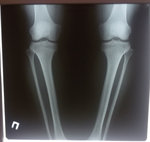

Ножки супер! разрешено всё без ограничений, все нагрузки: спорт, фитнес, каблуки любых размеров - Вам очень они пойдут! Нельзя: беременеть в течении первых 6 месяцев с момента снятия аппаратов!